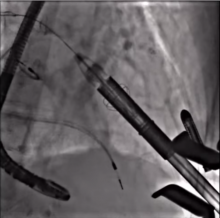

FORTIS Transcatheter Mitral Valve Implantation [1]

Vinnie Bapat of Guys and St. Thomas’ Hospital, London, UK, discusses the Edwards FORTIS device, a transcatheter mitral valve device, including the implantation technique and data from his early clinical experiences.